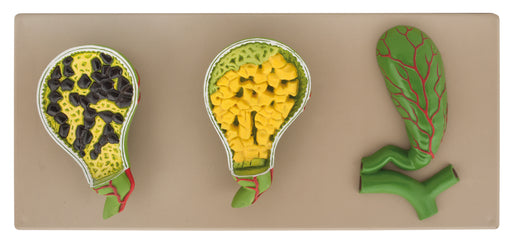

Gall Stones Set of 3

A relatively common disorder of the gall bladder, gall stones are formed by cholesterol or bile pigments settling in size from small half inch, one...

View full detailsam16046 -